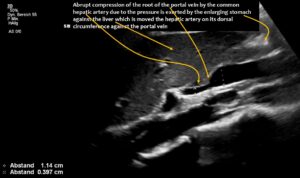

The enlargement of the superior mesenteric vein was due to compression of the root of the portal vein by the common hepatic artery. This resulted in an increasing outflow obstruction from both the distended superior mesenteric vein and the now curled splenic vein.

The longitudinal section showing the continuation of the superior mesenteric artery (SMA) into the root of the portal vein reveals an abrupt narrowing of the portal vein, caused by compression from the common hepatic artery.